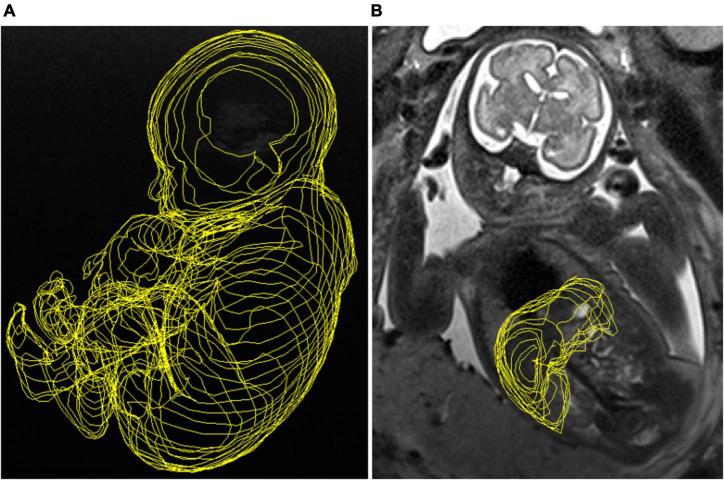

Most infected cases were diagnosed by the evidence of ultrasound abnormalities during routine scans and in some after maternal CMV screening. CMV-infected fetuses were considered severely or mildly affected according to prenatal brain lesions identified by ultrasound (US)/MRI. We assessed FLV, the FLV to abdominal circumference (AC) ratio (FLV/AC-ratio), and the FLV to fetal body volume (FBV) ratio (FLV/FBV-ratio). As controls, we included 33 healthy fetuses. Hepatomegaly was evaluated post-mortem in 11 cases of congenital CMV infection. Parametric trend and intraclass correlation analyses were performed.

There were no significant differences in FLV between infected ( = 32) and healthy fetuses. On correcting the FLV for AC and FBV, we observed a significantly higher FLV in CMV-infected fetuses. There were no significant differences in the FLV, or the FLV/AC or FLV/FBV-ratios according to the severity of brain abnormalities. There was excellent concordance between the fetal liver weight estimated by MRI and liver weight obtained post-mortem. Hepatomegaly was not detected in any CMV-infected fetus.

In CMV-infected fetuses, FLV corrected for AC and FBV was higher compared to healthy controls, indicating relative hepatomegaly. These parameters could potentially be used as surrogate markers of liver enlargement.